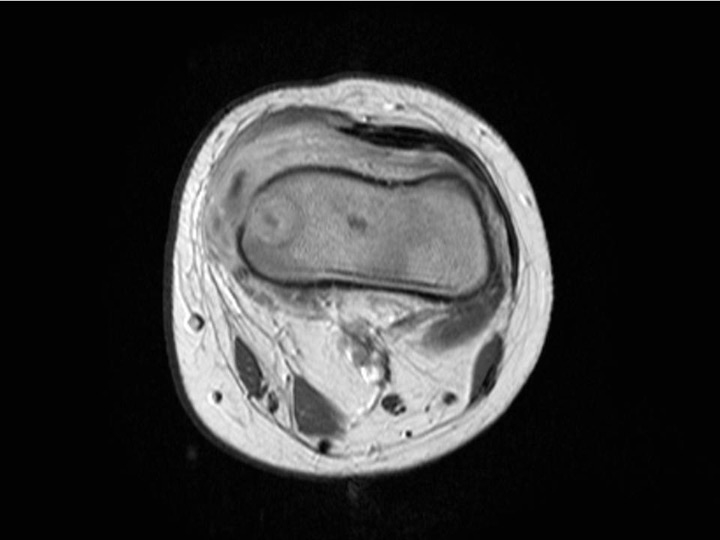

Figure 3

Magnetic resonance imaging (MRI) of the distal femur of a 17-month-old boy, which showed a normal appearance on plain radiographs. MRI demonstrated a lytic lesion of the distal femoral epiphysis with an important abscess of the soft surrounding tissues. Specific cultures confirmed tuberculosis.

PSAHO can be divided into two main clinical forms according to the age of the child and its bacteriological aetiology. The first form, the infantile form, affects children aged between 6 months to 4 years. Approximately 90% of all PSAHO affect patients in this age group with K. kingae as the main observed microorganism (personal data to be published). In these young children, the clinical course of PSAHO is most likely explained by the natural low virulence of K. kingae. K. kingae osteoarticular infection is characterised by a mild-to-moderate clinical and biologic inflammatory response to infection with few (if any) criteria evocative of OAI. Many children in this age group are usually recognised late as having an osteoarticular infection, and an accurate diagnosis is generally delayed until after a bony lytic lesion has occurred (fig. 3). The second form, the juvenile form, affects children older than 4 years and S. aureus appears as the main bacteriological aetiology. In this situation, PSAHO is most likely the result of an increased host resistance and it can be hypothesised that the children who develop this resistance against S. aureus become able to contain the bone infection. Indeed, colonisation is recognised to be more frequent among children [43]. Remarkably, 20% of individuals are persistently colonised by S. aureus in the nares and 30% are transiently colonised [44]. Although colonisation predisposes an individual to S. aureus infection, colonised individuals may have less severe S. aureus disease compared with non-colonised individuals [45]. This raises the question as to whether colonisation could induce low level, adaptive immunity and subsequent milder infections [44].